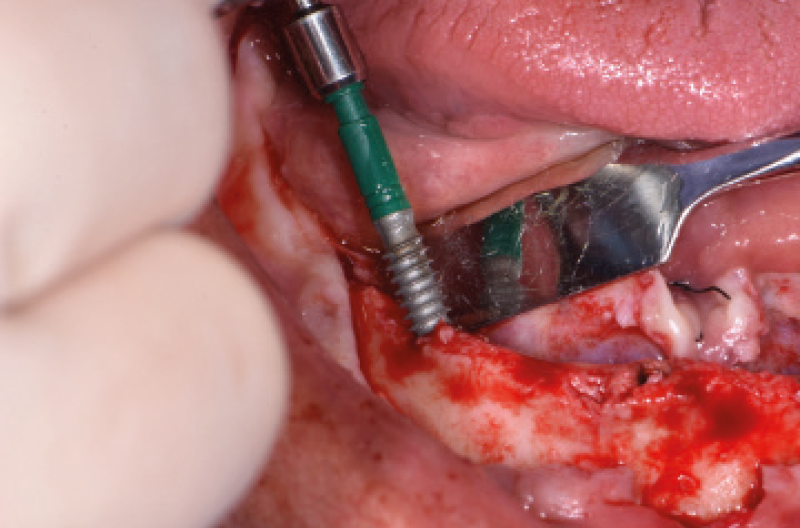

NellŌĆÖarcata inferiore ho posizionato distalmente 2 impianti Max Stability ├ś 3,75 mm L 12 e L 14 mm inclinati (ŌĆ£tiltatiŌĆØ) davanti ai forami mentonieri secondo il protocollo All-on-four, mentre nella zona sinfisaria ho inserito 2 impianti Narrow ├ś 2,9 L 12 mm (Figg. 15-20).

Fig. 19 – Inserimento degli impianti distali tiltati

Fig. 20 – Vista dei 4 impianti inseriti nellŌĆÖinferiore